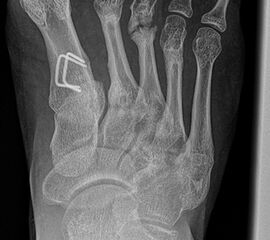

Abb. 2 a-c: offene Wachstumsfugen MT I Basis und Zehen (a), teilweise geöffnete Wachstumsfugen (b) und geschlossene Wachstumsfugen (c).

Zum Lesen der Bildbeschreibung und zur Vollansicht bitte die Bilder anklicken. Bilder: A. Helmers.